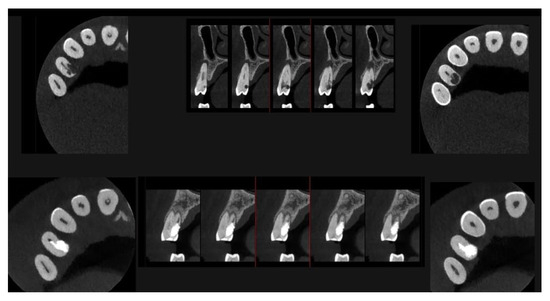

Figure 10.

Axial CBCT images of tooth 1.4 after six months of healing. (A–F) Sequential scrolling of the root of tooth 1.4 after six months of healing.

Figure 11.

Cross-section CBCT images of tooth 1.4 after six months of healing. (A–I) Sequential scrolling of EPL healing.

An intermediate follow-up CBCT scan at 6 months was performed to accurately assess the response to treatment in light of both the extent of the lesion and the patient’s systemic comorbidities (Figure 10, Figure 11, Figure 12, Figure 13 and Figure 14).